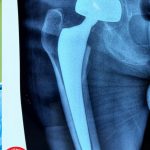

✨في إنجاز طبي جديد يُضاف إلى سجل النجاحات في مستشفى الحكيم العام أجرى فريق جراحة العظام عملية تبديل مفصل الورك الجزئي هذه المره لمريض معمر يبلغ من العمر (117) عاماً بعد تعرضه إلى كسر في عنق رأس عظم الورك الأيمن.

🔹 أُجريت له عملية تبديل مفصل الورك الجزئي (Hemiarthroplasty) بنجاح على يد الدكتور مصطفى الموسوي

أخصائي جراحة العظام والمفاصل والعمود الفقري وبمشاركة متميزة من الدكتورة فوزية عكاب – طبيبة التخدير